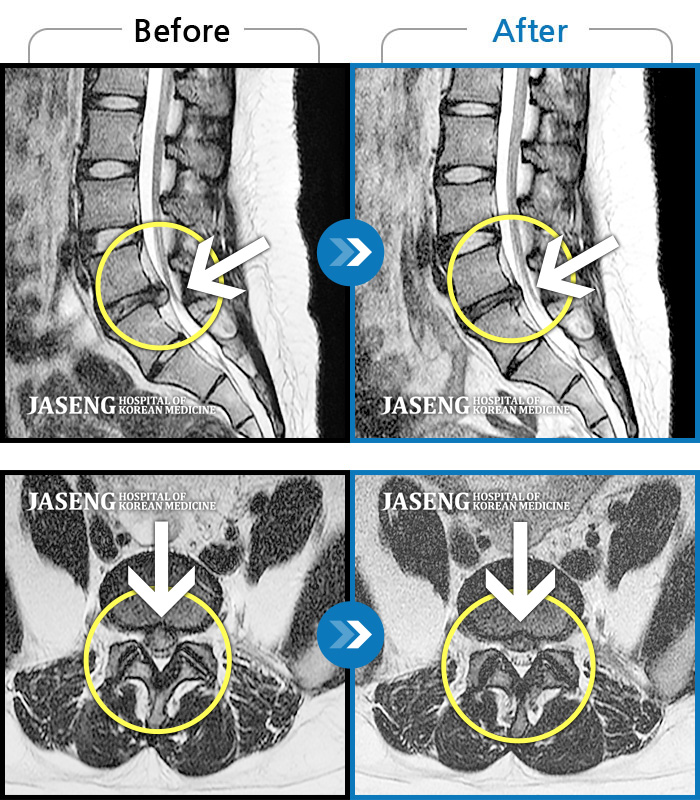

MRI 치료사례

허리 통증과 특히 왼쪽 하지 바깥쪽, 뒤쪽 통증